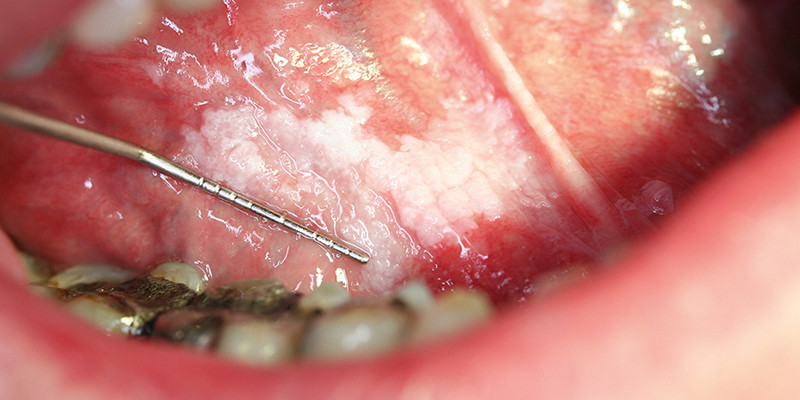

Tongcarcinoom komt zelden voor bij jongvolwassenen, maar naar verwachting stijgt de incidentie door een toename van infecties met het humaan papillomavirus. De huisarts kan een tongcarcinoom vaak van andere aandoeningen van de tong onderscheiden op basis van de anamnese en het lichamelijk onderzoek. Bij twijfel over de diagnose kan de kaakchirurg een biopt nemen. Wij beschrijven een casus van een 23-jarige patiënte met een pijnlijke zwelling van de tong, waarbij de aios de diagnose tongkanker aanvankelijk miste.